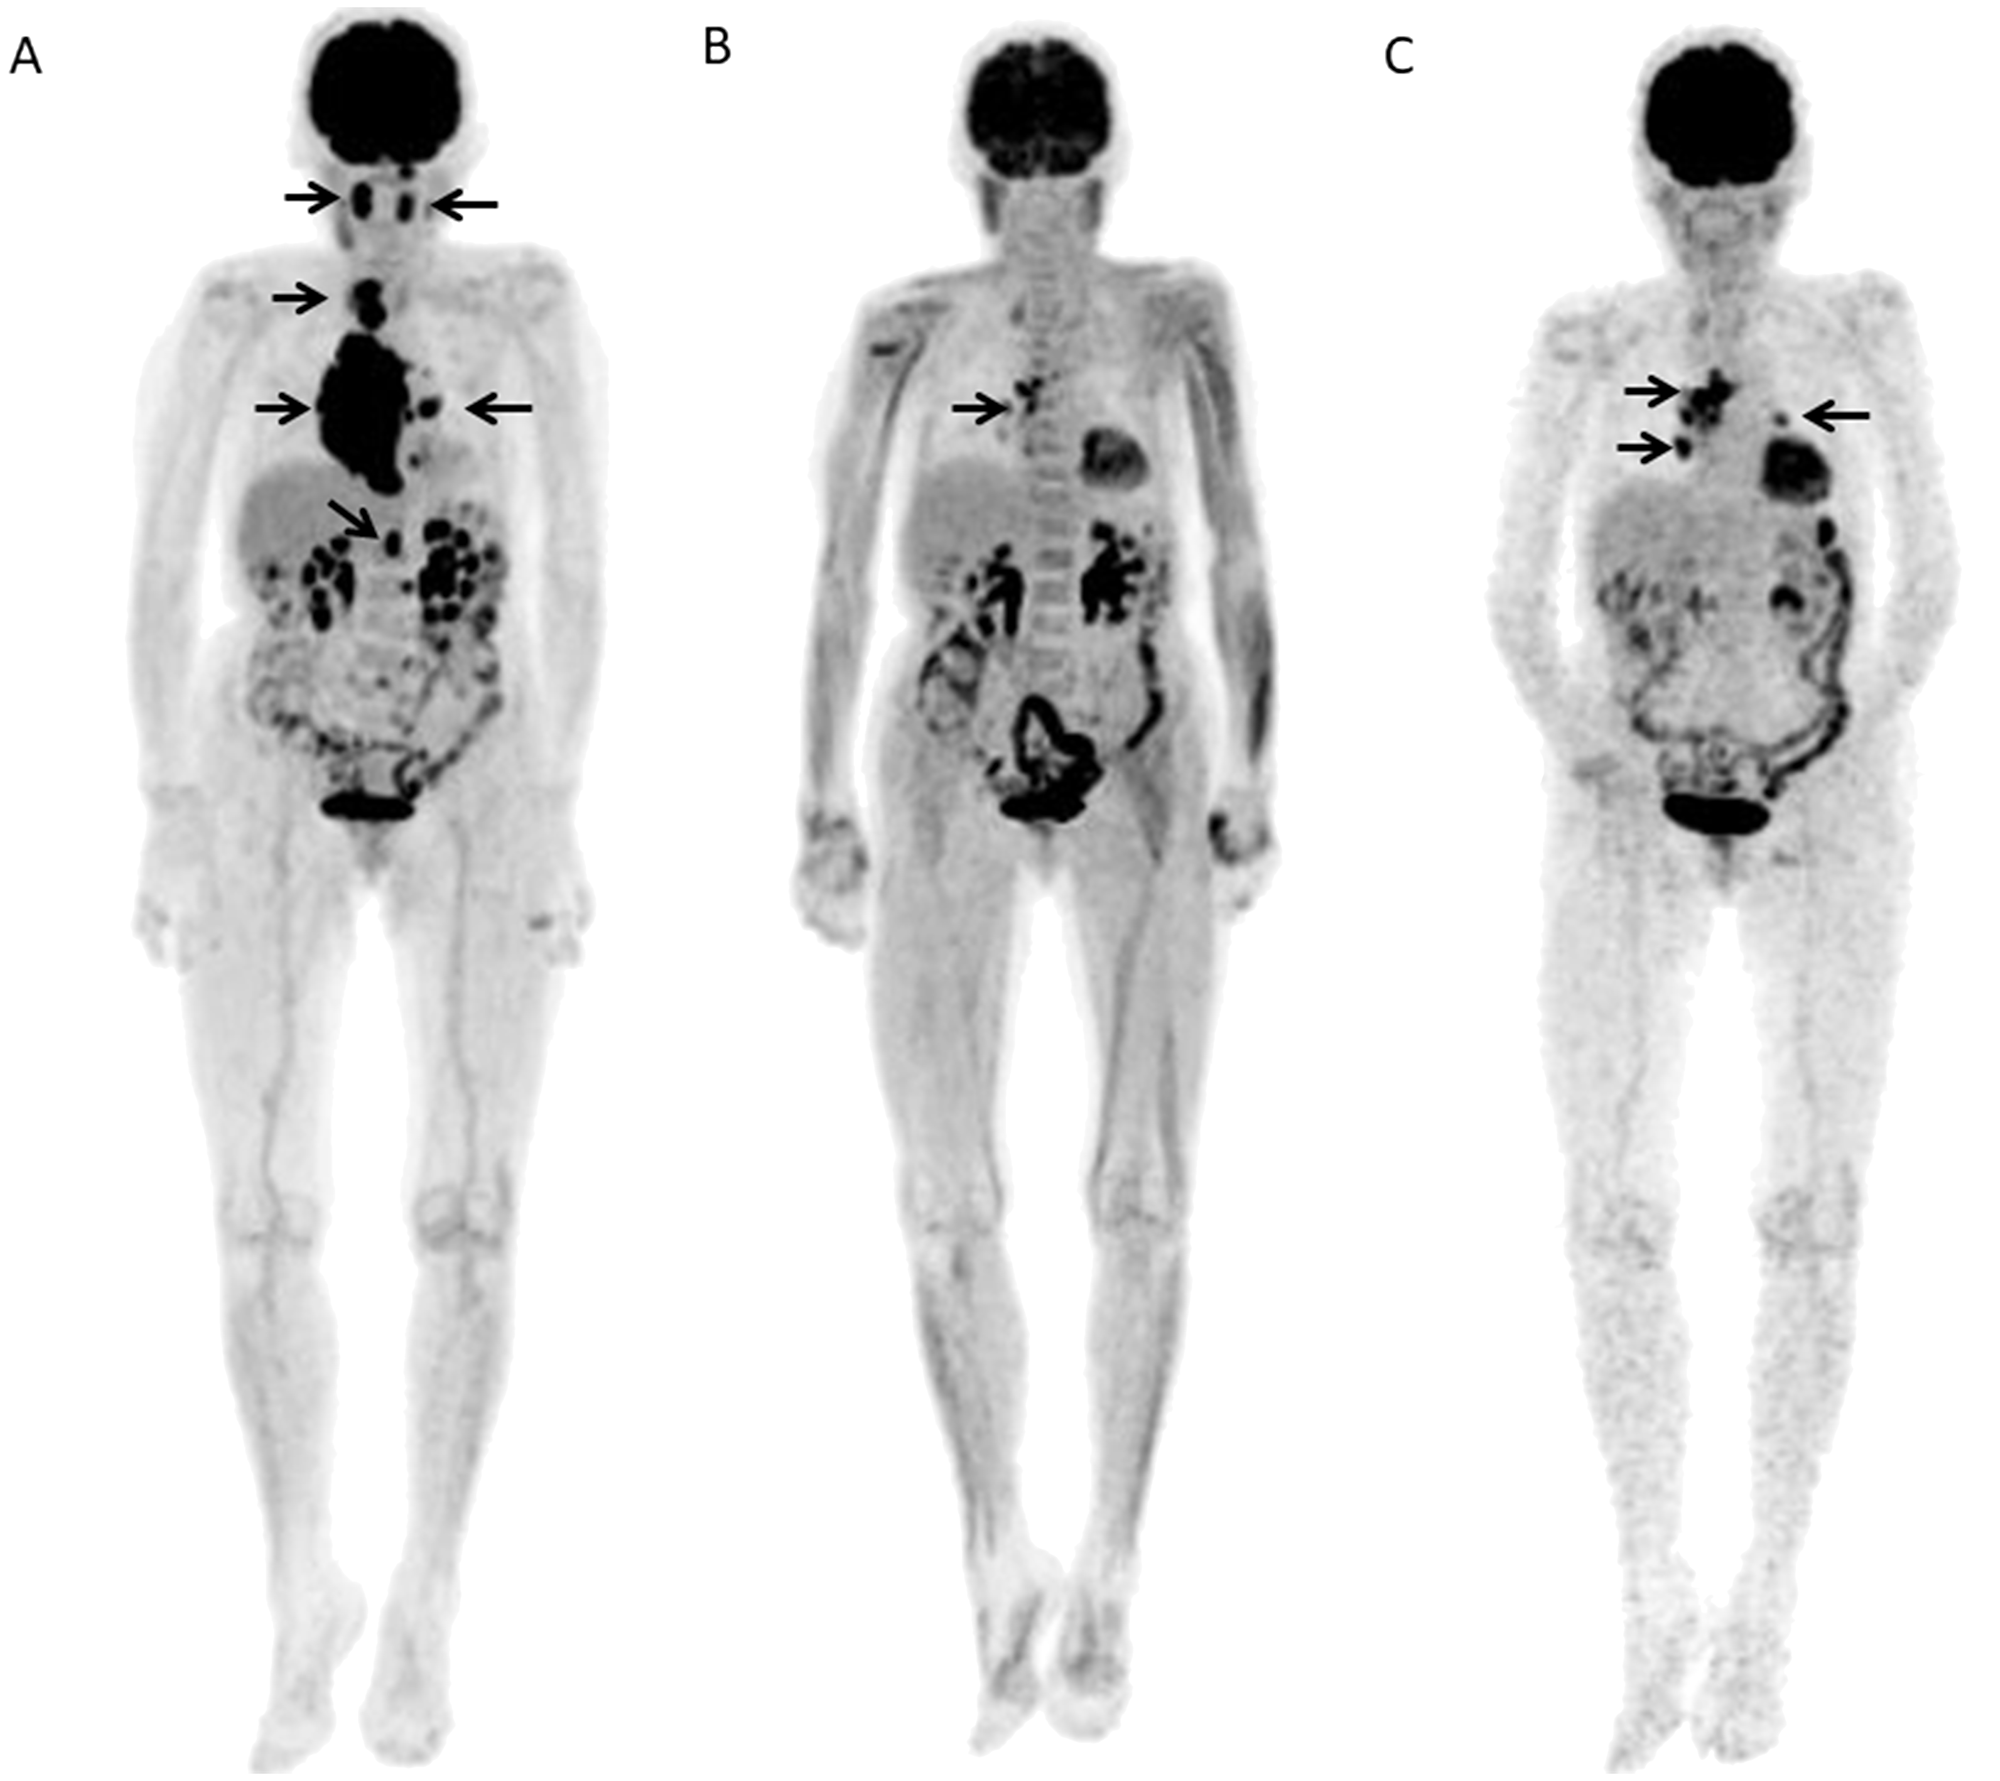

A 67-year-old female with DLBCL received 6 R-CHOP courses and no relapse was seen after 3.82 years

Figure 4: A 67-year-old female with DLBCL received 6 R-CHOP courses and no relapse was seen after 3.82 years. (A) Baseline FDG-PET maximum intensity projection (MIP) showed several areas of abnormal FDG uptake in right neck, abdomen, and left pelvis (arrows). (B) FDG-PET scan MIP after 2 courses of R-CHOP (Interim-PET) showed complete resolution of abnormal metabolic activity. (C) FDG-PET scan MIP after chemotherapy (End-PET) showed complete resolution of abnormal metabolic activity.